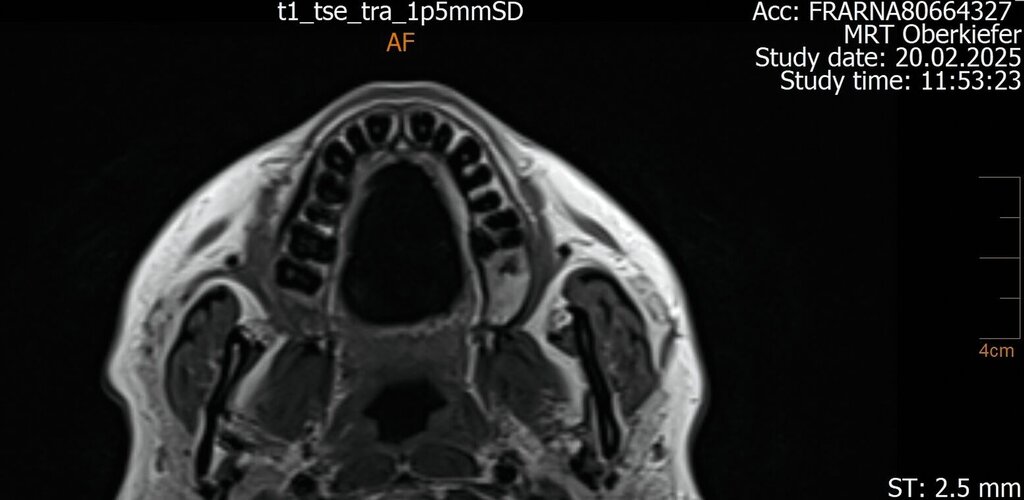

Der Wendepunkt erfolgte schließlich im Februar 2025 im Rahmen einer Kontrolluntersuchung bei der Hauszahnärztin. Diese nahm die langjährige Beschwerdesymptomatik ernst und veranlasste eine MRT-Untersuchung am Deutschen Zentrum für Dentaldiagnostik (DZD). Die MRT-Bildgebung ergab eine chronische Osteomyelitis im Bereich der Extraktionsregion von Zahn 27 sowie eine ausgeprägte apikale Ostitis an Zahn 26 mit vollständiger Verschattung der linken Kieferhöhle und Ausdehnung der Entzündung ins Siebbein und in die Stirnhöhle. Auch konnte durch den befundenden Radiologen eine interradikuläre Fistelung an Zahn 26 erkannt werden, weshalb die Sinusitis als odontogen eingestuft wurde (Abbildungen 4 bis 7).

Intraoperativ zeigte sich die interradikuläre Perforation im Sinne eines Fistelgangs zur linken Kieferhöhle (Abb. 8), die bereits präoperativ in der alio loco durchgeführten MRT-Bildgebung erkennbar gewesen war (Abb. 7). Zudem entfernten wir das Empyem und die pathologisch veränderte Schleimhaut sowie das Narbengewebe unter Schonung der noch intakten Schneider’schen Membran.